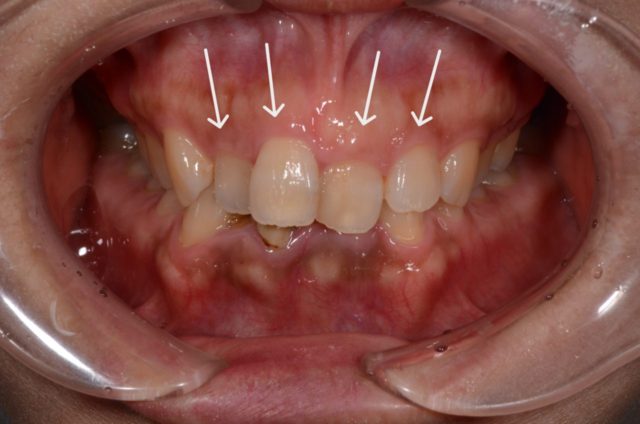

before

| 治療方法 | ジルコニアセラミッククラウンによる審美治療+ホワイトニングによる審美治療 (下の歯のホワイトニング後の色味よりもワンランク明るく作成) |

| 治療期間 | 3週間 |

| 費用 | 1,188,000円 |